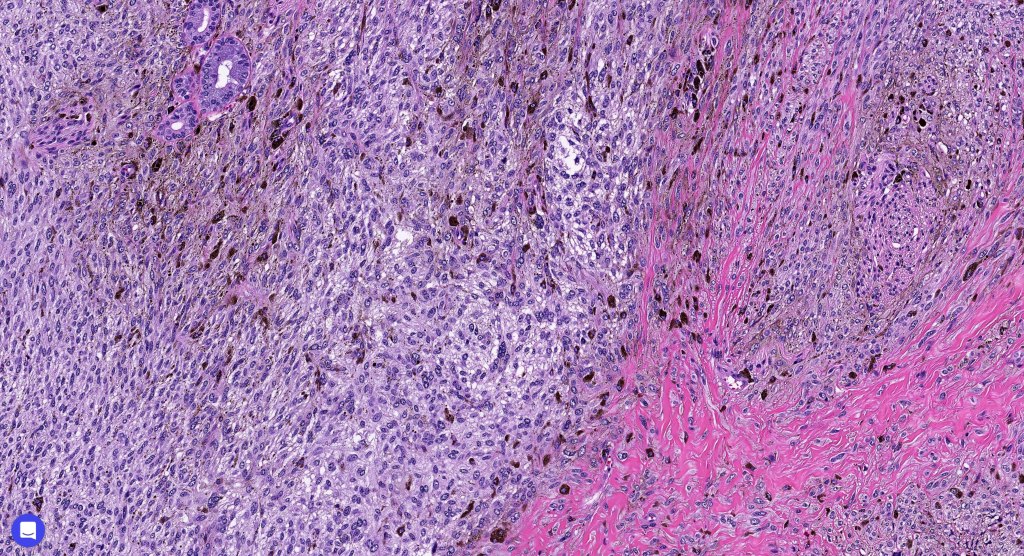

Histologically, it is characterized by a dense population of spindled, dendritic melnanocytes & melanophages with variable fibrosis. It may sometimes represent a component of a combined nevus. Mitotic activity is not usually present and pleomorphism is absent (see atypical blue nevus below). Involvement of the arrector pili muscle is not uncommon.

Very exceptionally, blue nevus also involves the epidermis (compound blue nevus).

•Most characteristic is the dumbbell silhouette although a plague morphology may also be encountered

•Admixture of spindle cells, pigmented bipolar or dendritic cells & melanophages

•An alveolar pattern is characteristic particularly with clear cell nodules

•Stromal fibrosis, myxoid change, vascular hyalinization with cyst formation are often seen

•Some tumors are composed spindle cells in a fascicular or neuronevoid pattern